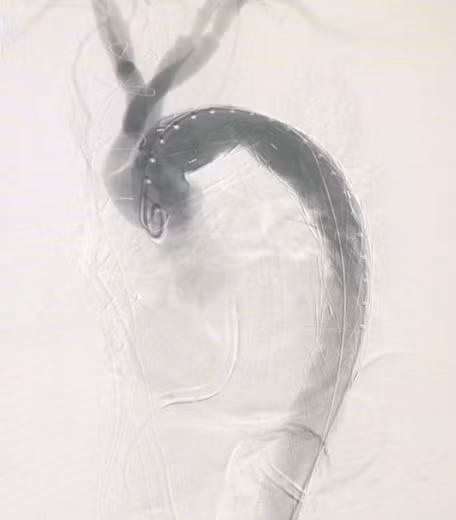

![]() |

| Hình ảnh lóc tách động mạch chủ sau can thiệp. |